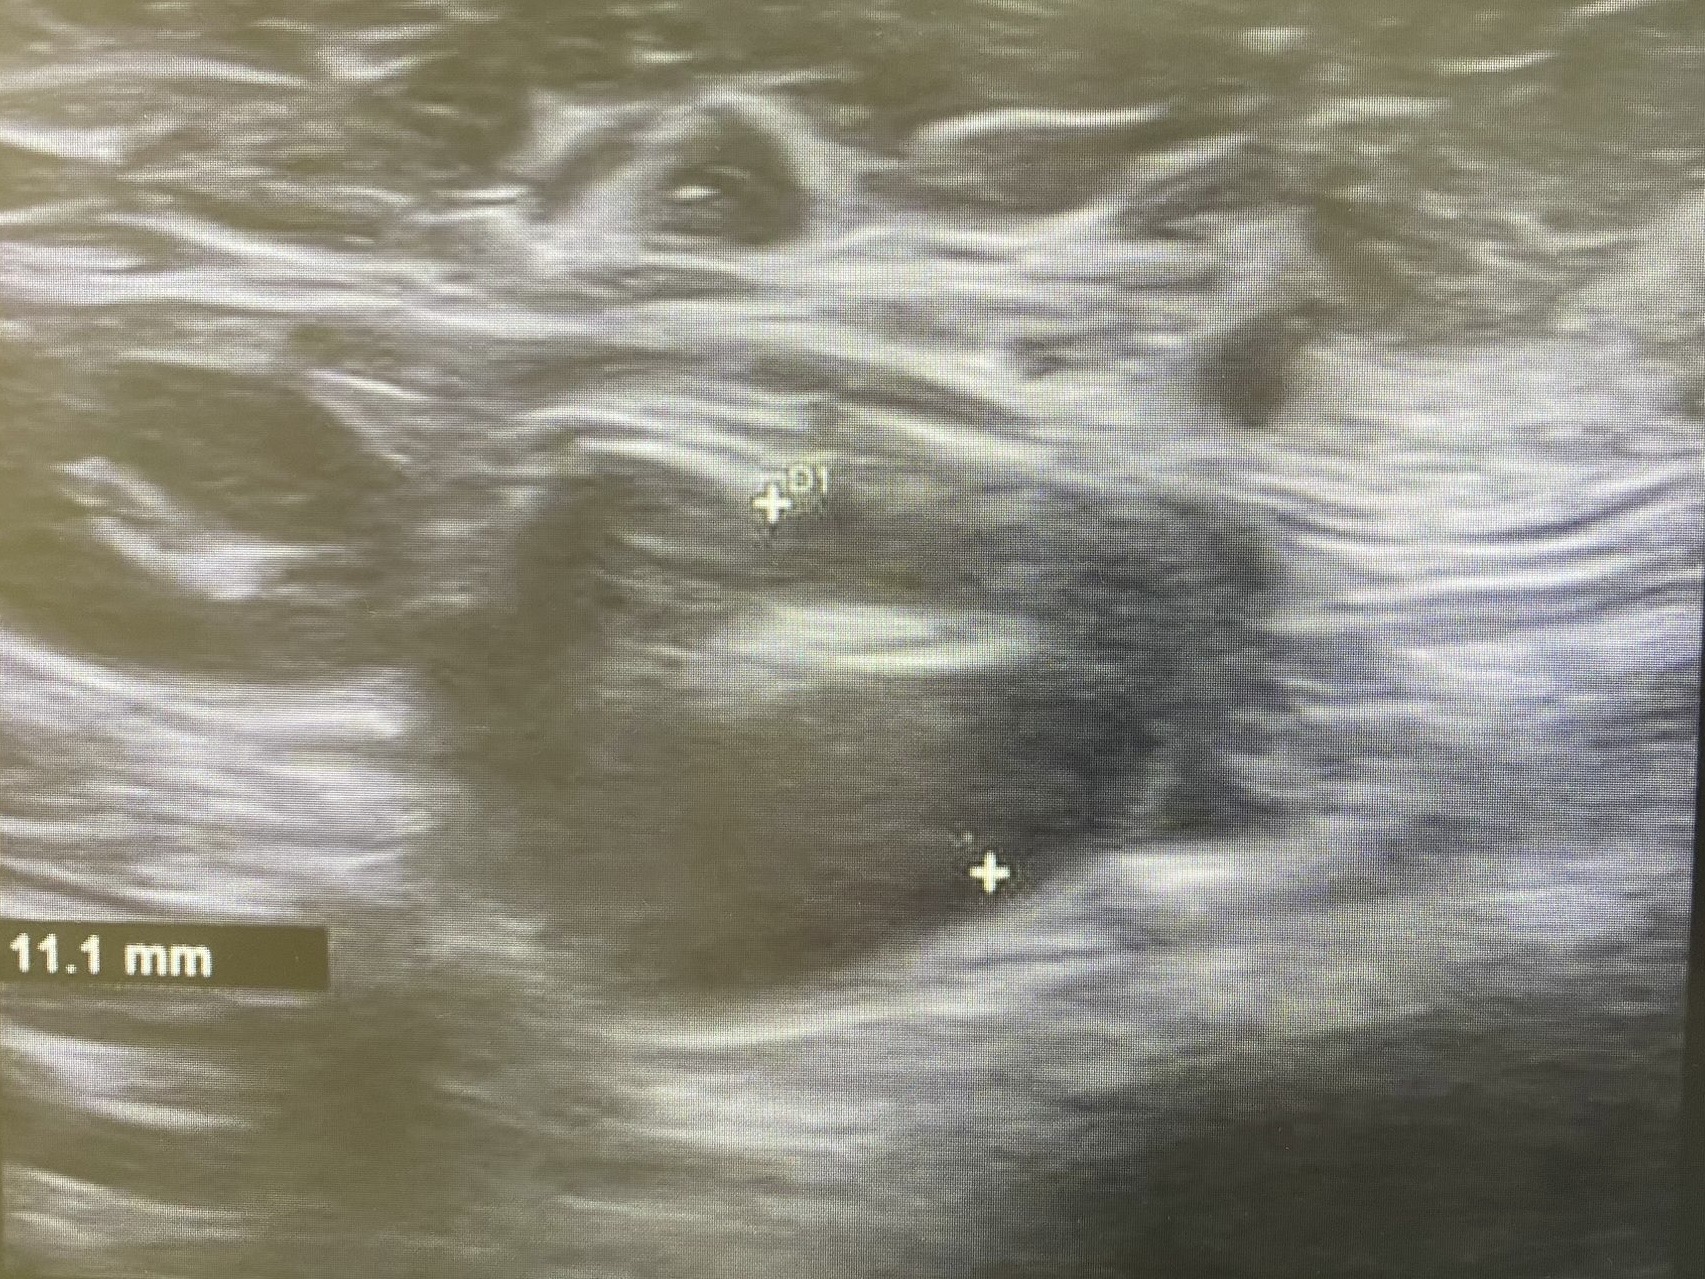

Ecografía: Valoración de adenopatías para acercamiento diagnóstico (típicas/atípicas).

Adenopatías patológicas, algunas redondeadas, con eje anteroposterior > 1 cm, parénquima homogéneo, cortical engrosada aunque con hilio respetado.

Ecografía axilar: múltiples adenopatías con eje corto > 2 cm y cortical engrosada.